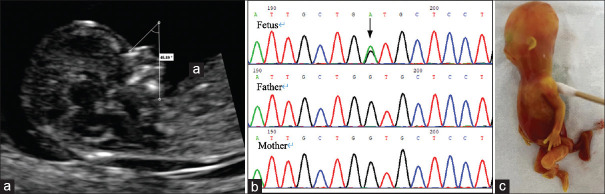

First-trimester Diagnosis of Micrognathia as a Presentation of Stickler Syndrome.